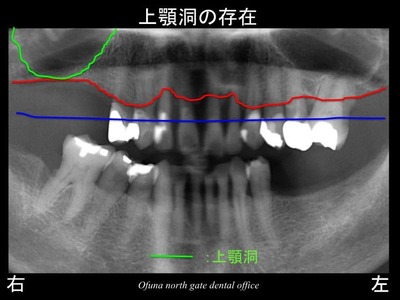

しかし、上顎右側の奥歯(欠損部)には大きな問題がありました。

上顎洞の存在です。

緑線の上方は上顎洞という空洞です。

空洞なのです。

骨ではなく、穴が開いているのです。

このように上顎の奥歯において

骨吸収が大きく、上顎洞の問題がある場合には、インプラントを埋め込むことが非常に困難なケースがあります。